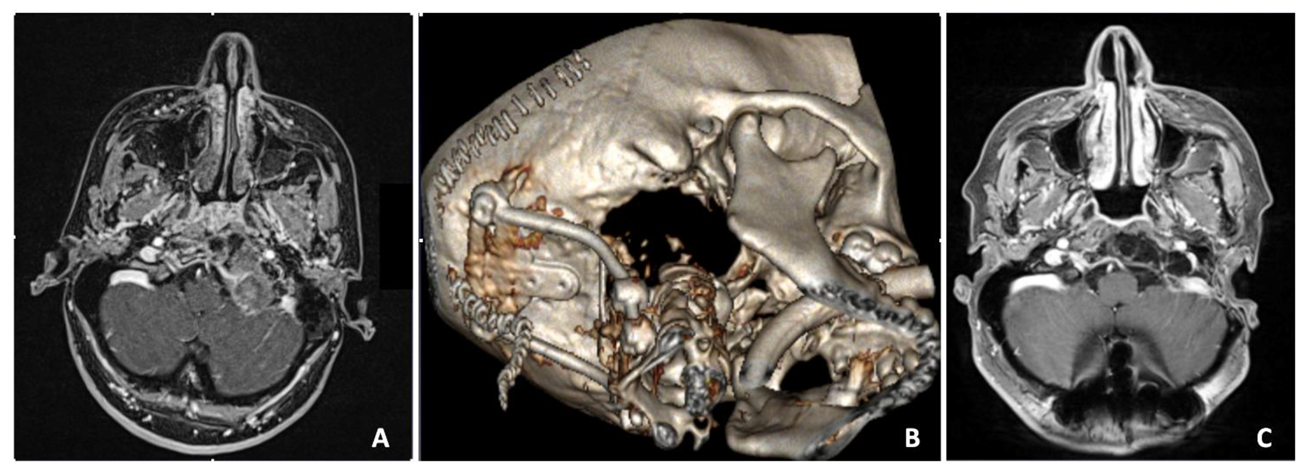

3.7. Case 7—Extradural Meningioma

| # 7 | 36 | F | Cervical pain | EEA FLA | Biopsy Resection | Extradural meningioma | Temporary left hypoglossal nerve palsy and rhinolalia | None | 5 years | Alive without disease |